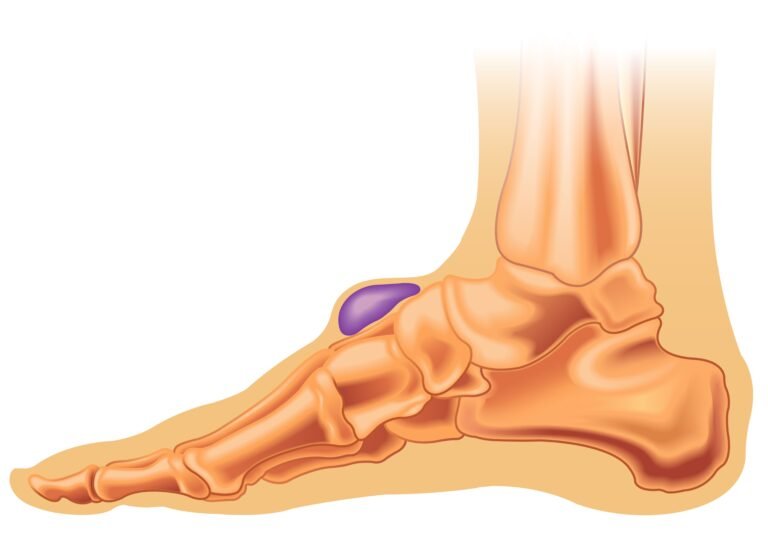

Steroid injections are an anti-inflammatory treatment for a wide range of painful joint and soft tissue conditions. They are often used to alleviate pain in inflammatory and degenerative joint and soft tissue conditions, such as rheumatoid arthritis, osteoarthritis, bursitis, and tendinitis. This article explores what steroid injections are, how they work, and what you can…